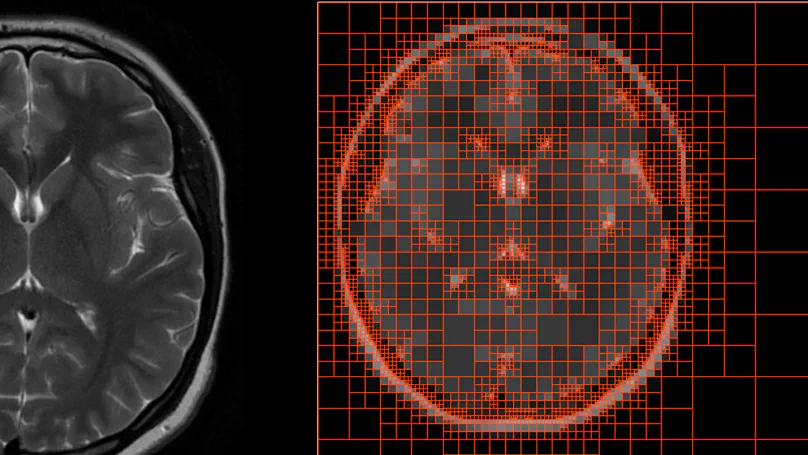

A unified, boundary-only SBFEM framework for nonlinear, viscoelastic, and anisotropic materials with direct applications in computational biomechanics.